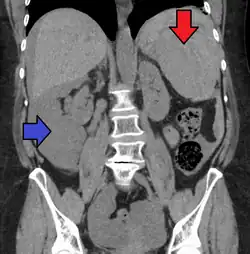

Splenic rupture is usually evaluated by FAST ultrasound of the abdomen.[5] Generally this is not specific to splenic injury; however, it is useful to determine the presence of free floating blood in the peritoneum.[5] A diagnostic peritoneal lavage, while not ideal, may be used to evaluate the presence of internal bleeding a person who is hemodynamically unstable.[6] The FAST exam typically serves to evaluate the need to perform a CT scan.[6] Computed tomography with IV contrast is the preferred imaging study as it can provide high quality images of the full peritoneal cavity.[5]

Organ injury scale

AAST (American Association for the Surgery of Trauma) Organ Injury Scaling: Splenic Injury Grading[7]

| Grade | Color | Subcapsular hematoma | Laceration |

|---|---|---|---|

| 1 | Blue | <10% surface area | <1 cm parenchymal depth |

| 2 | Green | 10–50% surface area | 1–3 cm parenchymal depth |

| 3 | Yellow | >50% surface area or expanding | >3-cm parenchymal depth |

| 4 | Orange | Major devascularization (>25% of spleen) | 25 – 75% of a splenic lobe |

| 5 | Red | Completely shattered spleen | >75% of a splenic lobe (or splenic avulsion) |

Calculators have been developed that facilitate grading of splenic injury based on imaging findings.[8]